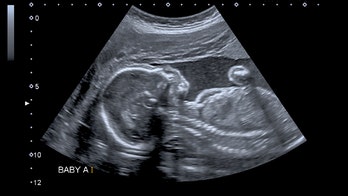

Pregnancy - Page 78